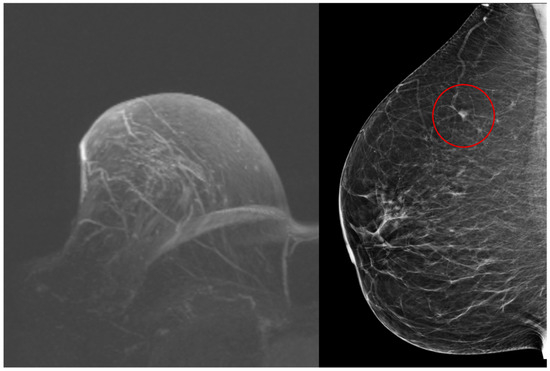

Invasive lobular carcinoma is the most common special subtype of invasive breast carcinoma. In addition to its specific morphology, it has different clinical, imaging, molecular, and treatment features compared to invasive breast carcinoma of no special type, as well as other special histologic subtypes.

- imaging

- diagnosis